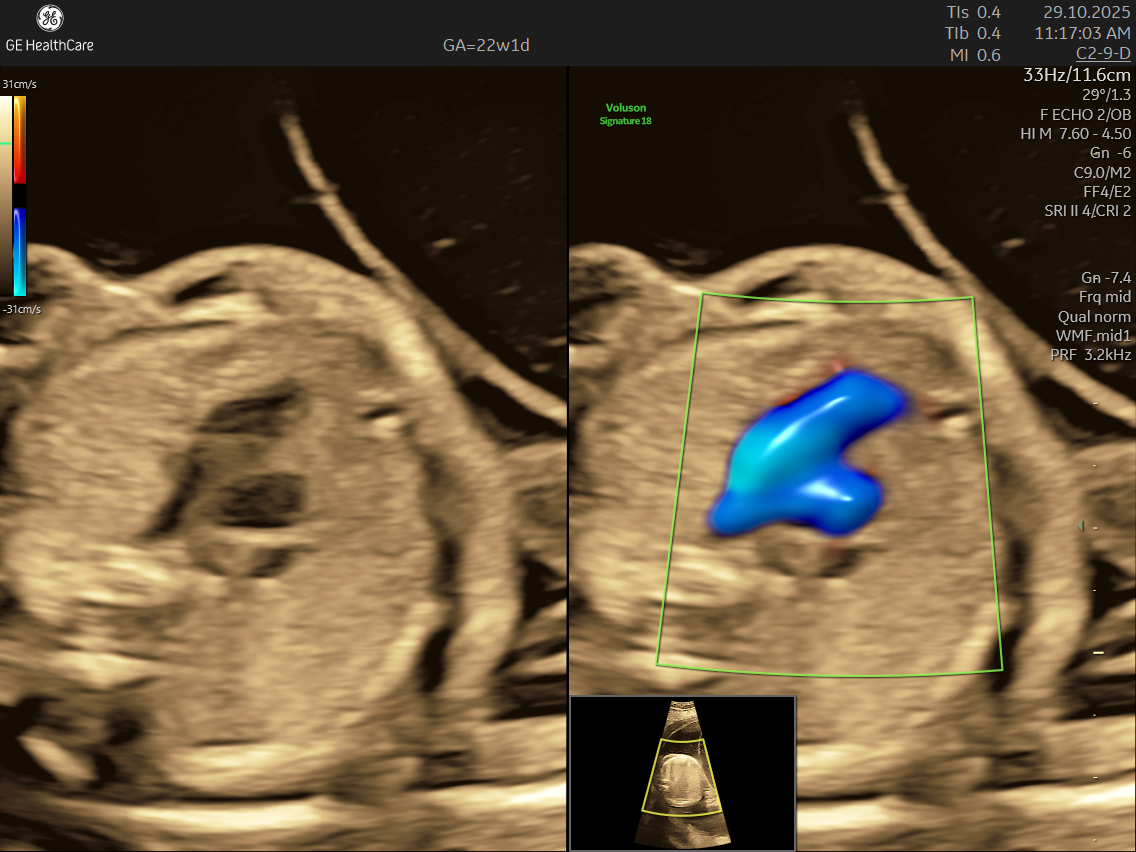

Fetal echocardiography is a valuabe early screening tool for Fetal Heart Defects. It is a specialized ultrasound scan that closely examines your baby’s heart while still in the womb. Unlike standard pregnancy scans, this test focuses on evaluating the structure, function, and rhythm of the fetal heart—providing incredibly detailed insights that help detect and diagnose congenital heart defects (CHDs) and other abnormalities early.

- High Detail: Utilizing advanced Doppler ultrasound technology, it tracks blood movement through the heart and valves, highlighting issues that general scans often cannot detect.

- Using the advanced GE Voluson S10 ultrasound machine—renowned for its superior imaging clarity, 4D real-time visualization, and automated analysis tools that significantly increase diagnostic accuracy and reduce the chances of missing subtle heart defects.

- Its a specialized ultrasound done between 18–24 weeks of Gestational Age that evaluates the structure, function, and rhythm of a baby’s heart while still in the womb. This scan uses high-frequency sound waves to create detailed images of the fetal heart, aiding in the detection of congenital heart defects (CHDs) and other abnormalities.